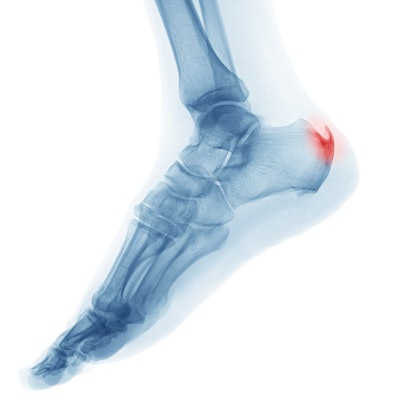

Test Yourself June 2019: Heel Spurs

[Image: Getty Images]